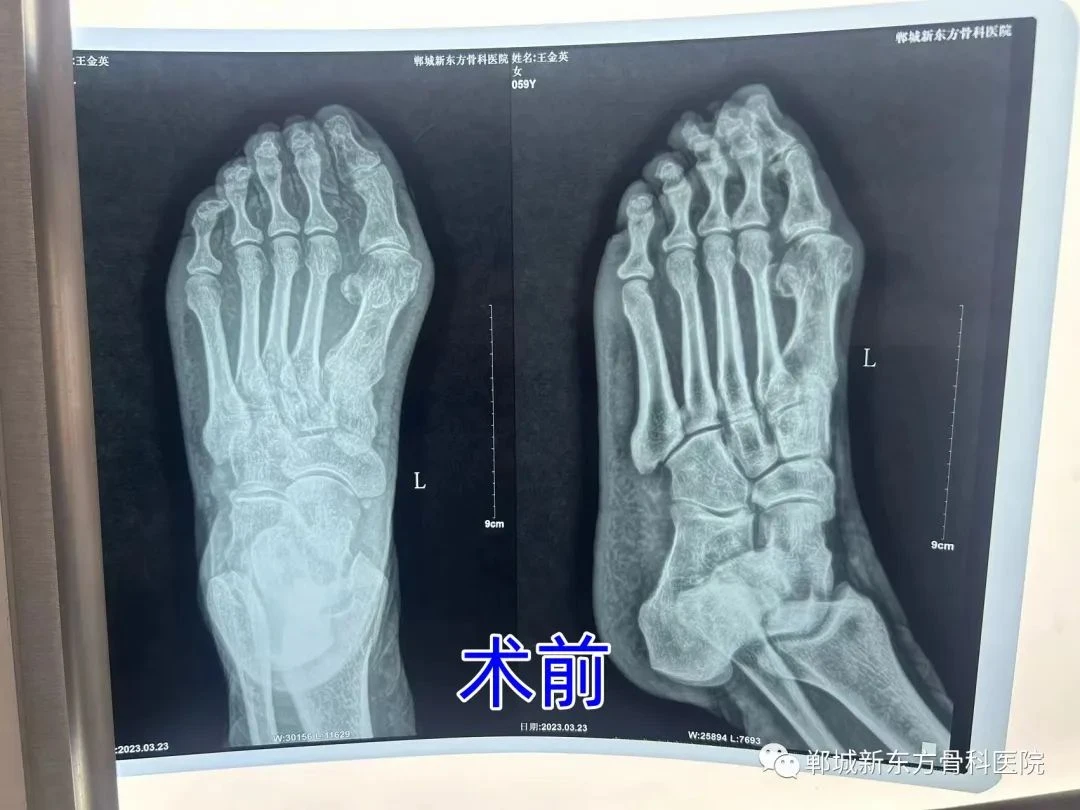

我县王女士,59岁,自诉5年前无明显诱因,走路出现疼痛,活动或者穿鞋都非常不便,门诊以“左拇外翻”收住入院。于3月23日行 趾闭关节融合术,手术非常成功,术后患者便可下床活动。经两个月随访,患者现在已恢复正常。